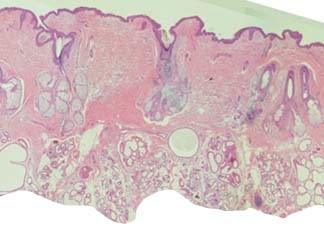

これは、ワキの皮膚の組織で,赤い線で囲まれた部分が汗の細胞です。この赤い線で囲まれた部分に大小とりどりのわっか 〇 があるのがわかりますか?

手術では皮膚の裏側(下側)から汗の細胞を削りとってきます。皮膚がだんだん薄くなってくるので、技術がなかったり、組織を見る目がないと、皮膚の浅い層にある汗の細胞が取り残されてしまいます。